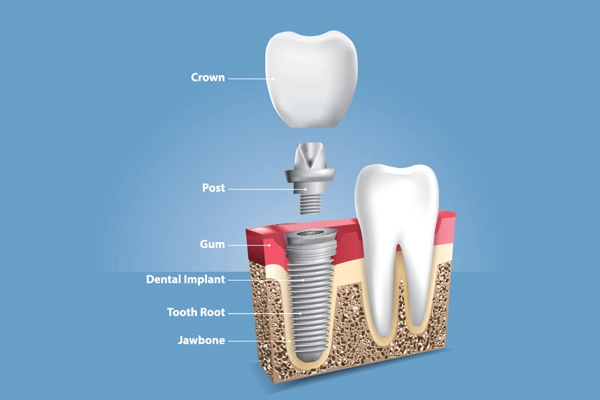

A dental crown is a cap placed over a tooth, serving to restore its shape, size, strength, and aesthetic appearance. Crowns are often recommended when a tooth is significantly decayed, fractured, or has undergone root canal treatment. They can also be used for cosmetic purposes, such as covering discolored or misshapen teeth.

- Completing root canal treatment: After the treatment, a crown provides the necessary protection to the treated tooth.

Tooth caps and dental crowns are terms that are often used interchangeably, but they have subtle differences. A tooth cap typically refers to a covering that is placed over a tooth, which is understood to have a more temporary or less extensive application than a dental crown. While dental crowns are custom-made to encase the entire tooth and are generally more robust, tooth caps might not offer the same level of protection or aesthetic enhancement.